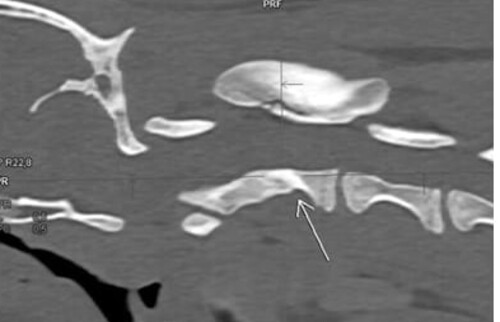

• An den Wirbelkörpern von C2 sind zwei frische Frakturlinien sichtbar, die auf akute Frakturen hinweisen, mit einer mittleren Frakturverschiebung (Verhältnis 1,39), was auf eine mittelstarke bis starke Verrenkung schließen lässt.

Abb. 3: Disclocation ratio = 1,39, was auf eine mittelstarke bis starke Verrenkung hindeutet